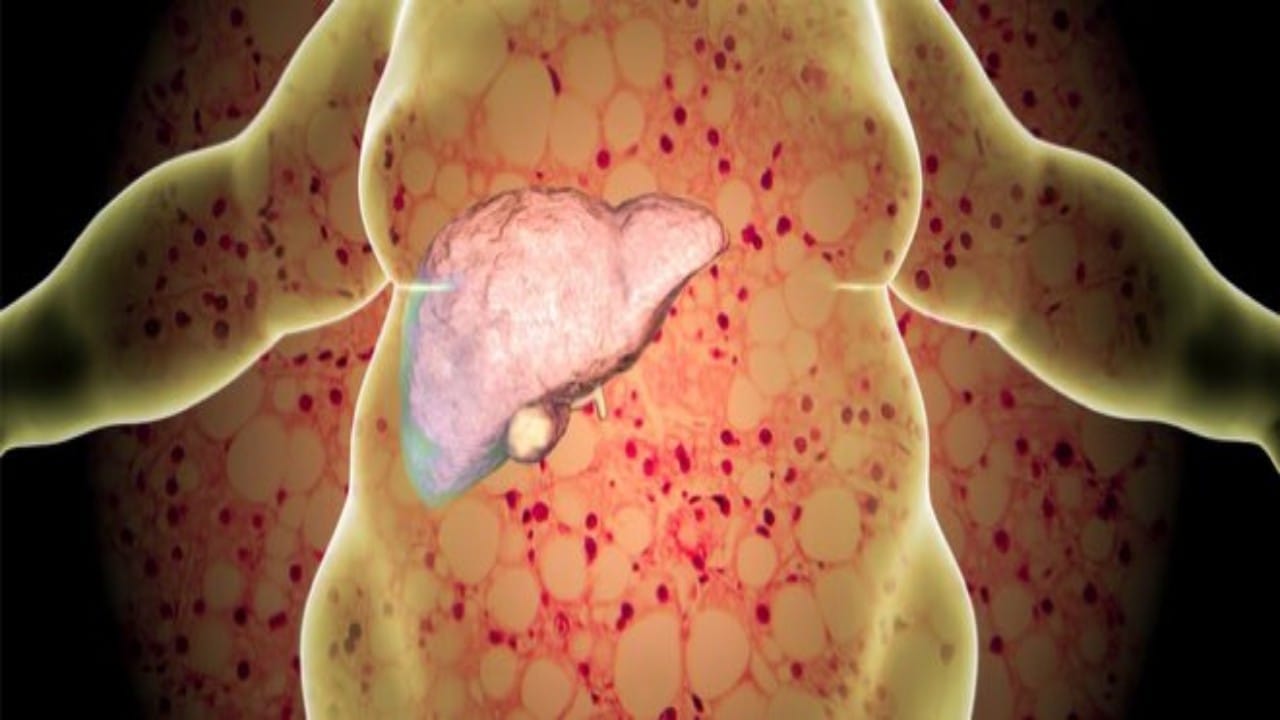

الذيابي: دهون الكبد مرض صامت لا يسبب عادةً أعراض